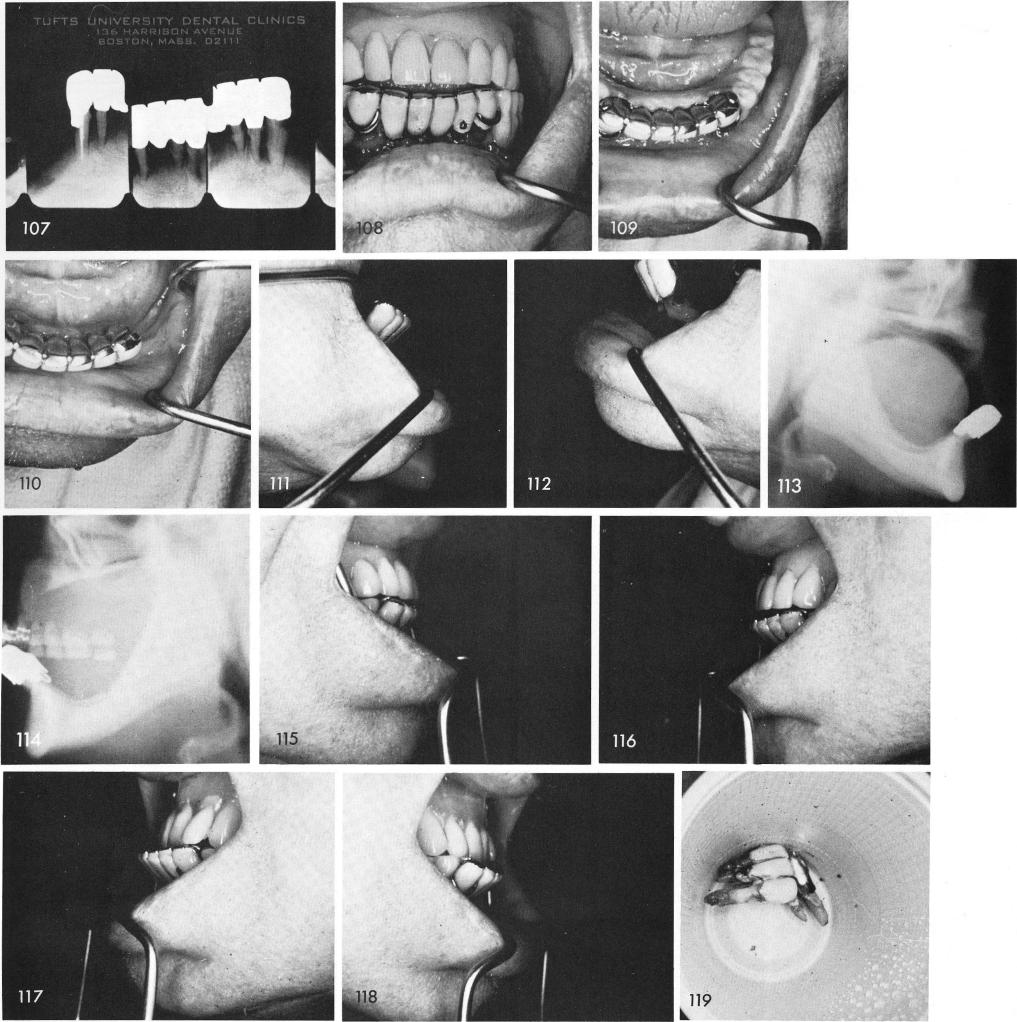

The preoperative periapical films show practically no bone above the inferior alveolar canals and condemned anterior teeth, fig. 107. Clinically, an open bite with a bilateral protrusion was seen, fig. 108. The anterior teeth flared out greatly in a labial direction, figs. 109, 110, 111, 112, 113. Fig. 114 demonstrates how far out labially the anterior teeth of his denture were brought forth to meet with the lower teeth. This distorted his entire face to such an extent that it closed his nostrils according to the patient. Profile views showing the over-extended denture, figs. 115, 116. A new denture was immediately fashioned so that the anterior teeth went be-hind the lower teeth by one half an inch, figs. 117, 118. The teeth were removed, figs. 119, 120,

1 Labial flaring of mandibular anterior teeth